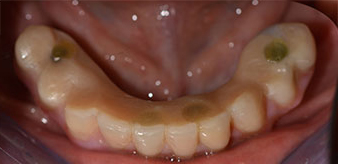

Un CT Scan à faisceaux coniques tridimensionnel (CBCT, Planmeca) a été réalisé au préalable afin de réduire les risques. Il a révélé une qualité et une quantité d'os disponible suffisante pour l'intervention chirurgicale et la restauration immédiate par la méthode All-on-four. En suivant le protocole de ce concept, les implants sont insérés au niveau de 35, 32, 42 et 45 en inclinant les implants distaux jusqu'à 45°, le profil d'émergence se déplace ainsi vers l'arrière et produit un polygone de stabilisation plus large (Fig. 3).